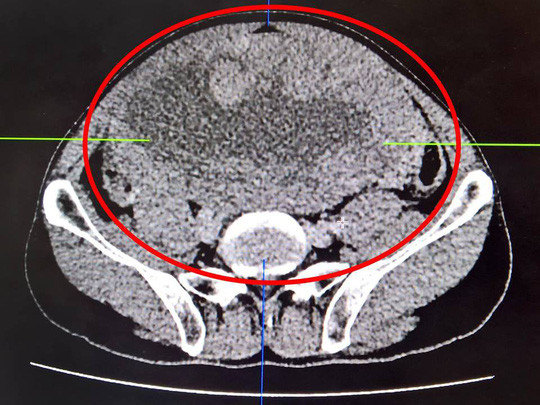

| Vị trí khối u chiếm trọn ổ bụng người đàn ông |

Ông V. đến khám trong tình trạng bụng đau kéo dài, ăn vào thấy đầy bụng, khó tiêu và ngày càng to. Kết quả kiểm tra cho thấy ổ bụng bệnh nhân có khối u lớn, khoảng 11 cm x 20 cm x 23 cm.